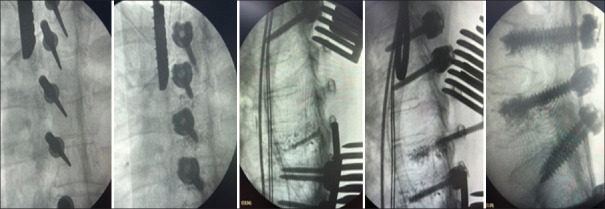

背景:聚甲基丙烯酸甲酯(PMMA)椎弓根螺钉增强术是一种用于降低机械并发症高风险患者椎弓根螺钉拔出、螺钉固定丢失和种植体失败风险的技术。研究设计:本研究为回顾性观察性研究。目的:本研究的目的是描述脊柱外科中传统椎弓根螺钉内固定的经典增强技术的改进。方法:回顾性分析47例65岁以上的脊柱手术患者,采用所建议的水泥增强技术,随访2年。将高粘度水泥注射到已攻丝的椎弓根内,然后置入传统椎弓根螺钉。患者的选择是基于详细的术前临床和影像学评估。测量的结果包括并发症的发生率,特别是水泥渗漏(CL),以及神经或血管缺损的发生率。结果:47例患者共使用700枚常规螺钉。700颗螺钉中有26颗(3.71%)出现CL。根据改进的Yeom分类,9/700(0.71%)为S型,9/700(0.71%)为B型,8/700(0.57%)为I型;没有神经或血管并发症。2年无机械并发症。结论:这种改良的椎弓根螺钉增强技术是老年患者脊柱内固定的一种替代方法,临床并发症发生率低,并且通过方便椎弓根螺钉置入减少了手术时间。

Methods: A retrospective analysis was performed on 47 patients over the age of 65 years who underwent spinal surgery using the proposed cement augmentation technique and were followed for 2 years. High-viscosity cement was injected into tapped vertebral pedicles, followed by the insertion of traditional pedicle screws. Patient selection was based on detailed preoperative clinical and imaging evaluations. Outcomes measured included the rate of complications, particularly cement leakage (CL), and the occurrence of neurological or vascular deficits.